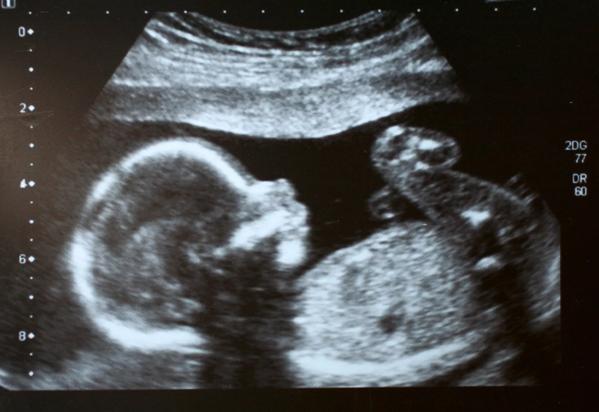

Fetus ultrasound

Cleveland Clinic has appointed Darrell Cass, M.D., as director of fetal surgery. In this role, Dr. Cass will lead a multidisciplinary team specialized in treating highly complex cases of birth defects, such as spina bifida, congenital diaphragmatic hernia, congenital cystic adenomatoid malformation (CCAM), sacrococcygeal teratoma, and other treatable fetal conditions.